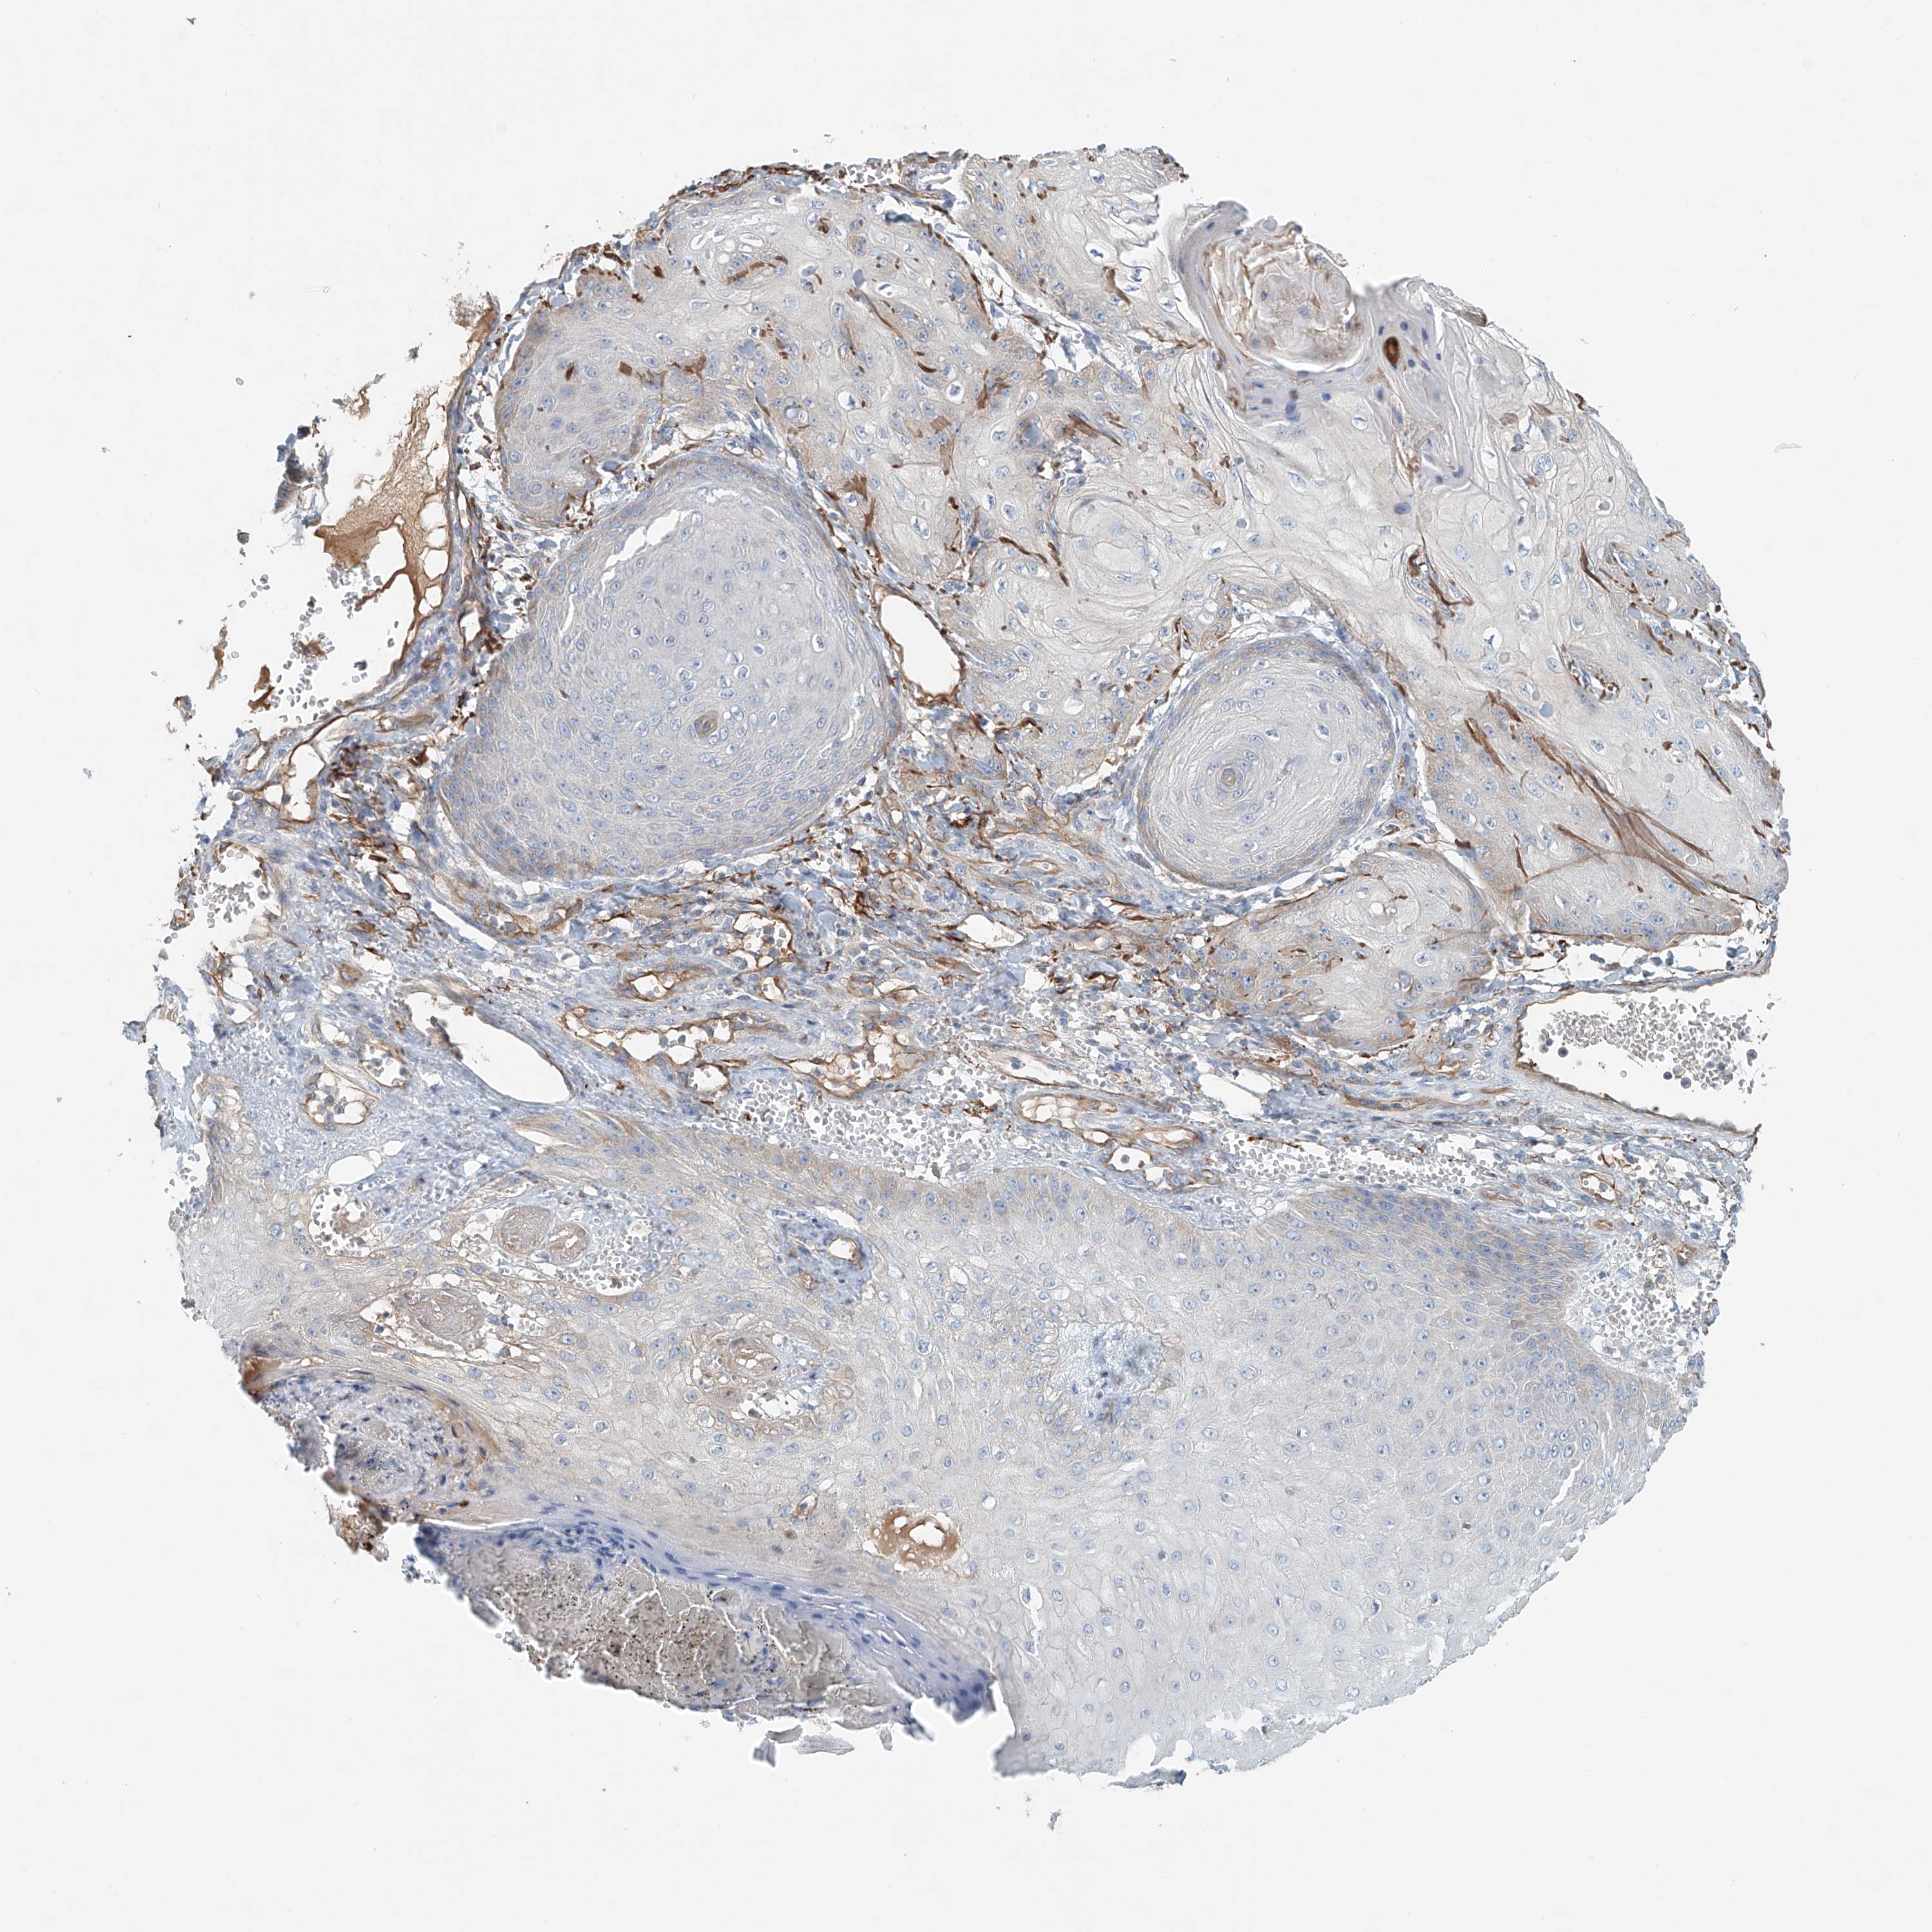

Basal cell and squamous cell cancer

SKIN CANCER - Protein expressioni

A mouse-over function shows sample information and annotation data. Click on an image to view it in a full screen mode. Samples can be filtered based on level of antibody staining by selecting one or several of the following categories: high, medium, low and not detected. The assay and annotation is described here.

Antibody stainingi

Antibody staining in the annotated cell types in the current human tissue is reported as not detected, low, medium, or high, based on conventional immunohistochemistry profiling in selected tissues. This score is based on the combination of the staining intensity and fraction of stained cells.

Each image is clickable and will lead to virtual microscopy that enables deeper exploration of all samples and also displays staining intensity scores, fraction scores and subcellular localization as well as patient and tissue information for each sample.

Antibody HPA031106

Antibody HPA031107

Staining

High

Medium

Low

Not detected

Intensity

Strong

Moderate

Weak

Negative

Quantity

>75%

75%-25%

<25%

None

Location

Nuclear

Cytoplasmic/membranous

Cytoplasmic/membranous,nuclear

Basal cell carcinoma